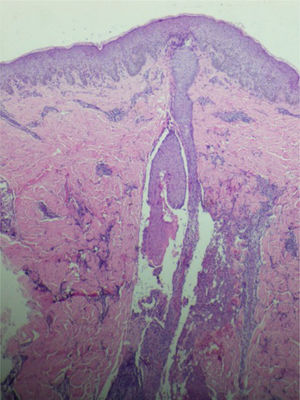

Paciente do sexo feminino, 26 anos, primigesta, no curso de 31 semanas de gestação, relatava aparecimento de lesões cutâneas pruriginosas no tronco, com dois meses de evolução. Ao exame físico, observavam‐se pápulas eritematosas e pústulas localizadas no abdome (em especial na linha nigra), no esterno, dorso e na face lateral dos glúteos (figs. 1 e 2). Foram solicitados exames laboratoriais e realizada biópsia de pústula do dorso. Os exames laboratoriais não revelaram anormalidades, e a análise histopatológica evidenciou infiltrado perivascular predominantemente linfocítico na derme, além de folículo piloso permeado por infiltrado inflamatório com predomínio de neutrófilos e destruição da estrutura folicular (figs. 3 e 4). A paciente foi tratada com gel de peróxido de benzoíla a 5% e apresentou regressão completa das lesões na primeira semana pós‐parto.